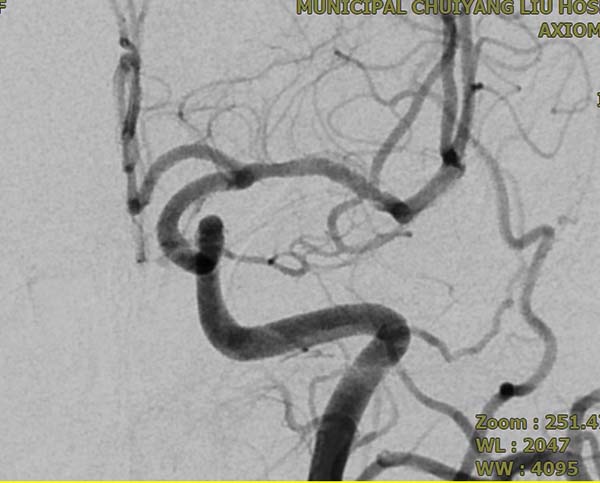

▲术后3个月复查DSA

为精准把握手术指征与安全,术前,需完善全脑血管造影对动脉瘤的形态、大小及载瘤动脉的血管条件进行全面评估;术中,需由经验丰富的神经介入医生精准将密网支架植入病变部位;术后,患者需严格遵医嘱服用抗血小板药物,以预防支架内血栓形成及缺血性卒中事件的发生,并需定期复查全脑血管造影,以评估动脉瘤的最终闭塞情况。本例患者行密网支架植入术后三个月复查全脑血管造影,结果显示密网支架贴壁良好,无支架内血栓形成,继续用药和定期复查即可。